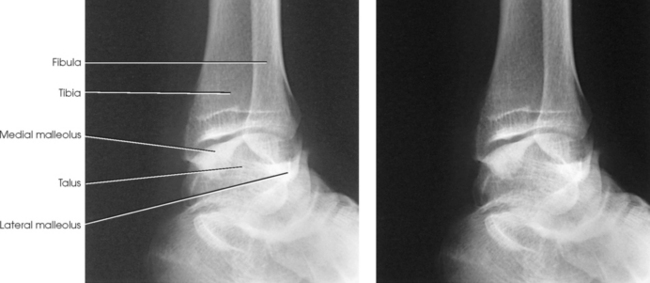

Structures shown: The entire ankle mortise joint should be shown in profile. The three sides of the mortise joint should be visualized (Figs. 6-102 and 6-103).

Fig. 6-102 AP oblique ankle, 15- to 20-degree medial rotation to show ankle mortise joint. A, Properly positioned leg to show mortise joint. B, Poorly positioned leg; radiograph had to be repeated. The foot was turned medially (white arrow), but the leg was not. Lateral mortise is closed (black arrow) because the “leg” was not medially rotated.

Fig. 6-103 Axial drawing of inferior surface of the tibia and fibula at the ankle joint along with matching radiographs. A, AP ankle position with no rotation of the leg and foot. Drawing shows lateral malleolus positioned posteriorly when leg is in true anatomic position. Radiograph shows normal overlap of anterior tubercle and superolateral talus over fibula (arrows). B, AP oblique ankle, 15- to 20-degree medial rotation to show ankle mortise. Drawing shows both malleoli parallel with IR. Radiograph clearly shows all three aspects of mortise joint (arrows). C, AP oblique ankle, 45-degree medial rotation. Radiograph shows tibiofibular joint (arrow) and entire distal fibula in profile. Larger upper arrow show wider space created between tibia and fibula as leg is turned medially for two AP oblique projections. This space should be observed when ankle radiographs are checked for proper positioning.